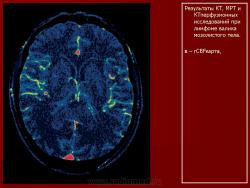

Лимфомы головного мозга.